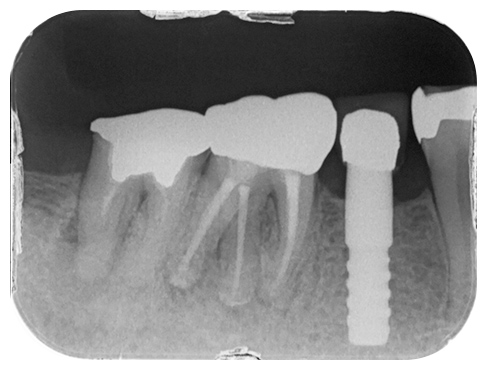

専門医になるには特別なプロフラムを2年以上学び、卒業後、自分の専門分野のみの治療や研究、教育を行わなければなりません。当院では、レントゲン検査にて診断した上で、米国歯内療法学会認定の専門医が行う世界基準の歯内療法も場合により、ご提案致します。